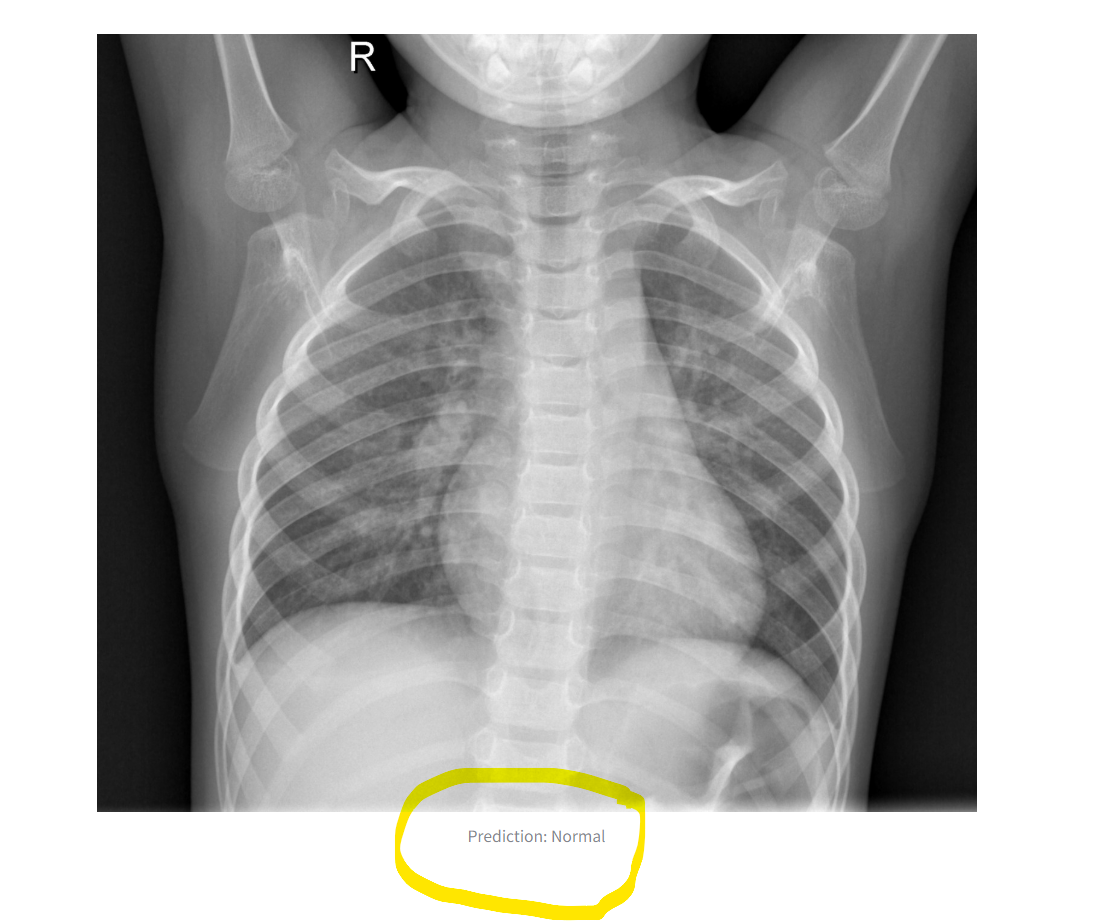

The application demonstrates reliable performance on test images. It accurately distinguishes between "Normal" and "Pneumonia" cases when provided with valid X-ray images. Results are displayed directly in the Streamlit interface, making it accessible for non-technical users. See the image below:

The output image and label